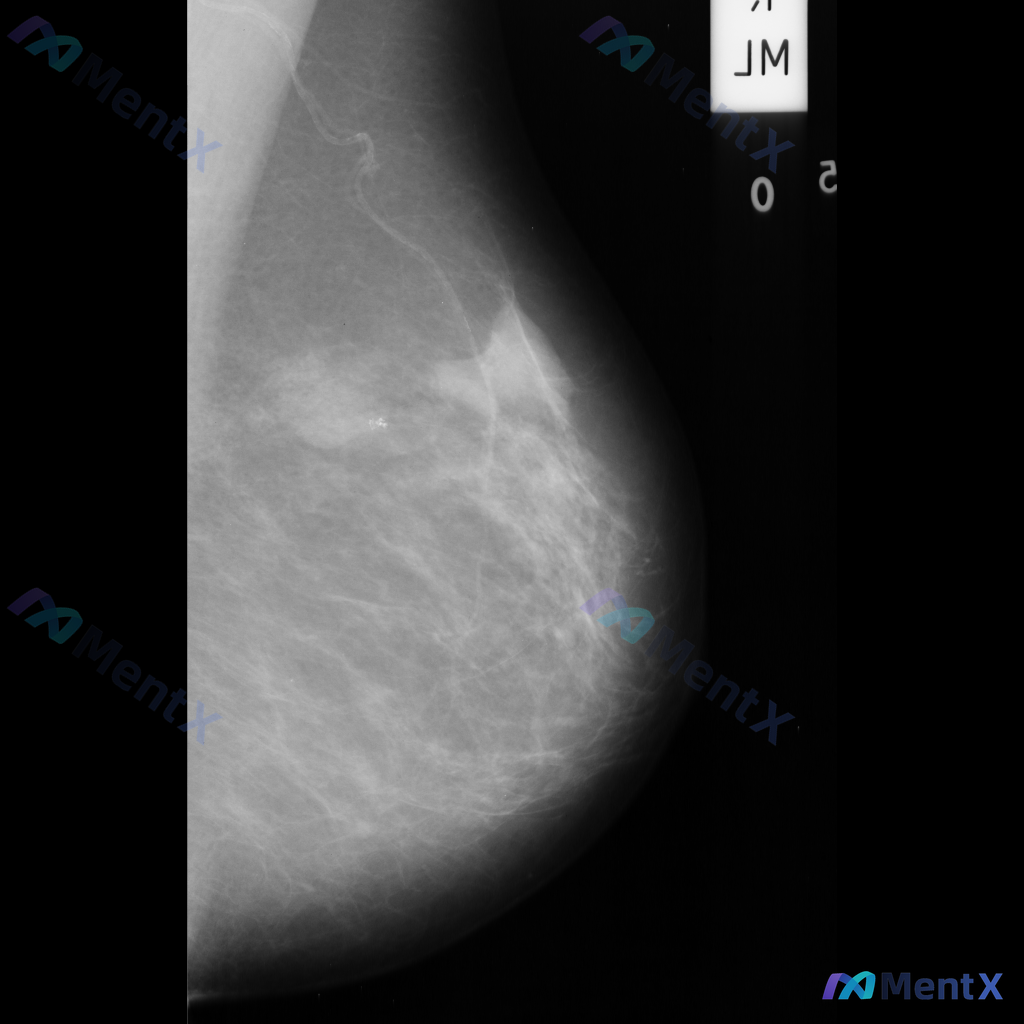

影像表现:

- 病灶位于乳腺上中部(大致外上象限)可见一局限性高密度肿块影

- 形态不规则,边缘有毛刺状改变

- 周围腺体结构有扭曲、牵拉征象

- 肿块内部或附近可见点状钙化,部分呈簇状分布